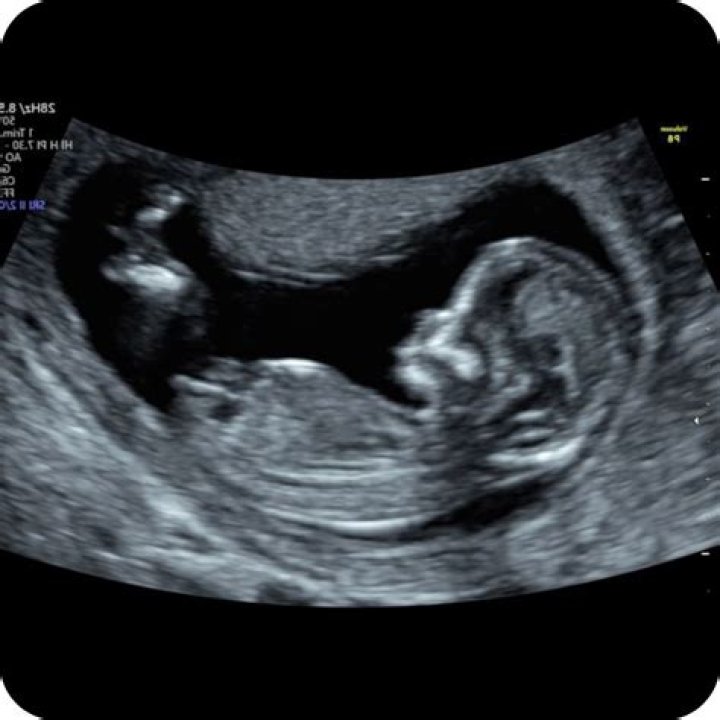

How big is a 12 week scan

At 12 weeks, the foetus is now about the size of a passion fruit, measuring close to 5.5 cm, crown to rump, and weighing approximately 18 grams.

Basic anatomy is visible on the 12-14 week ultrasound. Your medical provider can see if the heart has four chambers; if the brain has two hemispheres; and if the baby has eyes, limbs, lungs, a spine and a bladder, said Dr.

The 12-week ultrasound is usually an external scan. (In occasional cases, an internal — known as transvaginal — scan may be necessary if the external scan can’t produce a clear image.) You’ll lie back on the exam table, and an ultrasound technician will apply a clear gel across your lower belly.

“For the most part, the 12-week rule exists because most woman have an ultrasound scan at 12 weeks,” she says. “That’s really become the benchmark for women to feel like the pregnancy is real.” Dr Nash says historically, the 12-week ultrasound either did not exist or was not standard practice during pregnancy.